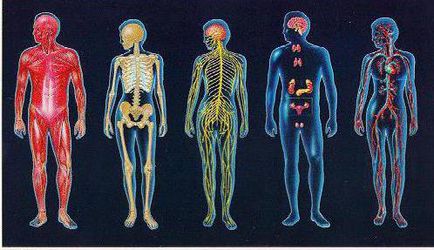

Az emberi test - egy organizmus, ahol az intézkedés az összes szervek és rendszerek szorosan összefügg. Az alapvető egység a sejt. Mire elérik a felnőttkort emberi test egy átlagosan három milliárd sejt. Mindegyikük alakított szervek, beolvadt a rendszer, amelyek mindegyike fontos szerepet játszik az életben. Rendszerek az emberi test:

- Szív- és érrendszer. Ez magában foglalja a kapillárisok, artériákat, vénákat szív. A fő funkciója a rendszer vért pumpál, elküldi az összes szerveket. A bal oldala a szív - „pumpa” az egész test, a jobb oldalán a szívizom szállít vért a tüdőbe gazdagítása érdekében, hogy oxigénnel. A szív három rétegből (szívizom, epicardiumban, szívbelhártya). Mindegyikük rendelkezik egy eltérő sűrűségű és a funkcionalitás.

- A nyirokrendszer. A fő funkciója - a kitermelés és szállítás a nyirok a testen keresztül.

- Izomrendszer. Ez áll az emberi csontváz, amelyben a csontok egy vonalban vannak egymással ízületek által támogatott izmok kapcsolódnak a vázhoz inak. A tanulmány az emberi test gyakran kezdődik vizsgálata a vázszerkezet. Általában, a csontváz áll 206 csontok.

- Az idegrendszer. Az idegrendszer hordozza a szervezet felelős információt a test és a környezet. Osztva perifériás és centrális.